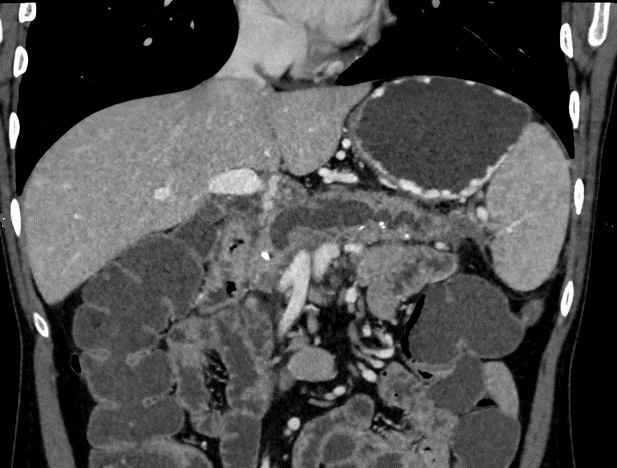

Pancreas volumineuse a

isodense, , bord irregulier .avec des calcifications

nodulaires ou multiforme tres hyperdense dissemine

intra parenchymateuse du pancreas . Image

radiologique TDM d'une pancreatite chronique

primitive en coupe axiale . |